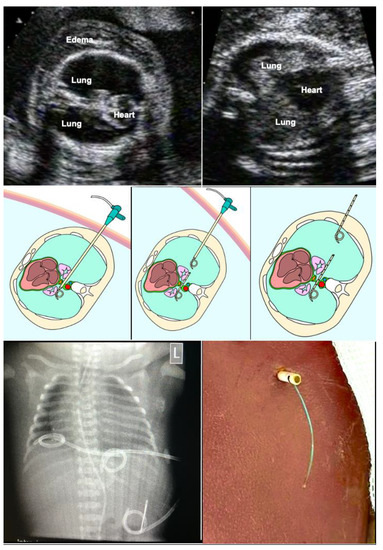

Bilateral fetal hydrothorax may result in severe cardio-pulmonary compression with subsequent cardiac failure, ascites and massive skin edemas. Hydropic fetuses are at risk of dying from progressive decreases in fetoplacental blood flow, aggravated by placental dysfunction. In some cases, even the mother develops hydropic changes, mirroring the fetal disease (“Mirror”-Syndrome). In this situation, bilateral fetal thoraco-amniotic shunting is a lifesaving approach for about 50% of hydropic fetuses. Most commonly, double-pigtail catheters have been inserted into either chest cavity. Depending on fetal lie and activity, intrathoracic needle insertion and the placement of the external pigtail end may require extensive manipulations, thus increasing the risk of the premature rupture of membranes. Given the limited length of most devices, the procedure may be even more difficult or technically impossible in cases with massive skin edema (Figure 10).

Figure 10.

Bilateral thoraco-amniotic drainage from a single insertion site. Top left—before the intervention, bilateral hydrothorax with severe pulmonary and cardiac compression as well as marked skin edema are observed at 26 weeks of gestation. Top right—after the intervention, the lungs are distended again and cardiac filling has improved. Technique: middle left—without manipulation of fetal position or amniotic fluid augmentation, a catheter sheath is placed closely above the diaphragm from the proximal into the distal thoracic cavity. Via the sheath, an adequately trimmed single pigtail catheter (about 5 cm) is placed across the midline such that it connects both chest cavities. Middle center—then, the sheath is pulled back into the proximal chest cavity. Middle right—here a second catheter is placed, extending from the proximal chest cavity for about 6 cm into the surrounding amniotic cavity and uterine wall. Following passive drainage of the bilateral effusions via the catheter sheaths and catheters, the catheter sheath is removed without further manipulation and the maternal abdominal skin incision is closed with a single stitch. As soon as the fetus awakens from anesthesia and begins to move again, it pulls the distal end of the catheter into the amniotic cavity, thus completing the procedure.

In order to overcome the limitations of the current techniques, bilateral thoraco-amniotic drainage from a single insertion site is possible without the need for manipulation of fetal position (Figure 10). It puts little strain on the uterine wall and membranes and does not require amniotic fluid augmentation. The procedure is performed under materno–fetal anesthesia and usually lasts only a few minutes. All of the materials are widely available in hospitals with adult and pediatric intensive care.

In short, following a small maternal skin incision, an 18-gauge T-fastener needle is inserted dorso-laterally into the lower third of the fetal chest cavity that is nearest to the anterior uterine wall (Figure 10). After unloading the T-fastener and securing the fetal position by fixation of its suture, the needle is advanced closely above the diaphragm—crossing the midline between the thoracic aorta and esophagus—into the contralateral chest cavity. Then, a 0.035′′ guide wire is inserted through the needle shaft, followed by removal of the needle. The wire serves as a rail for the insertion of an 8-F-catheter sheath. Via the sheath, an adequately trimmed single pigtail catheter (about 5–7 cm) is placed across the midline such that it connects both chest cavities. Then, the sheath is pulled back into the proximal chest cavity. Here a second catheter is placed, extending from the proximal chest cavity into the surrounding amniotic cavity and uterine wall. Following passive drainage of the bilateral effusions via the catheter sheaths and catheters, the catheter sheath is removed without further manipulation and the incision is closed with a single stitch. As soon as the fetus awakens from anesthesia and begins to move again, it pulls the distal end of the catheter into the amniotic cavity, thus completing the procedure.

Following delivery, the external end of the catheter can be employed for further drainage or serve as a rail for exchange with a new catheter. The midline crossing pigtail and the T-fastener remain in the chest and can be removed electively by thoracoscopy around two to three years of age.